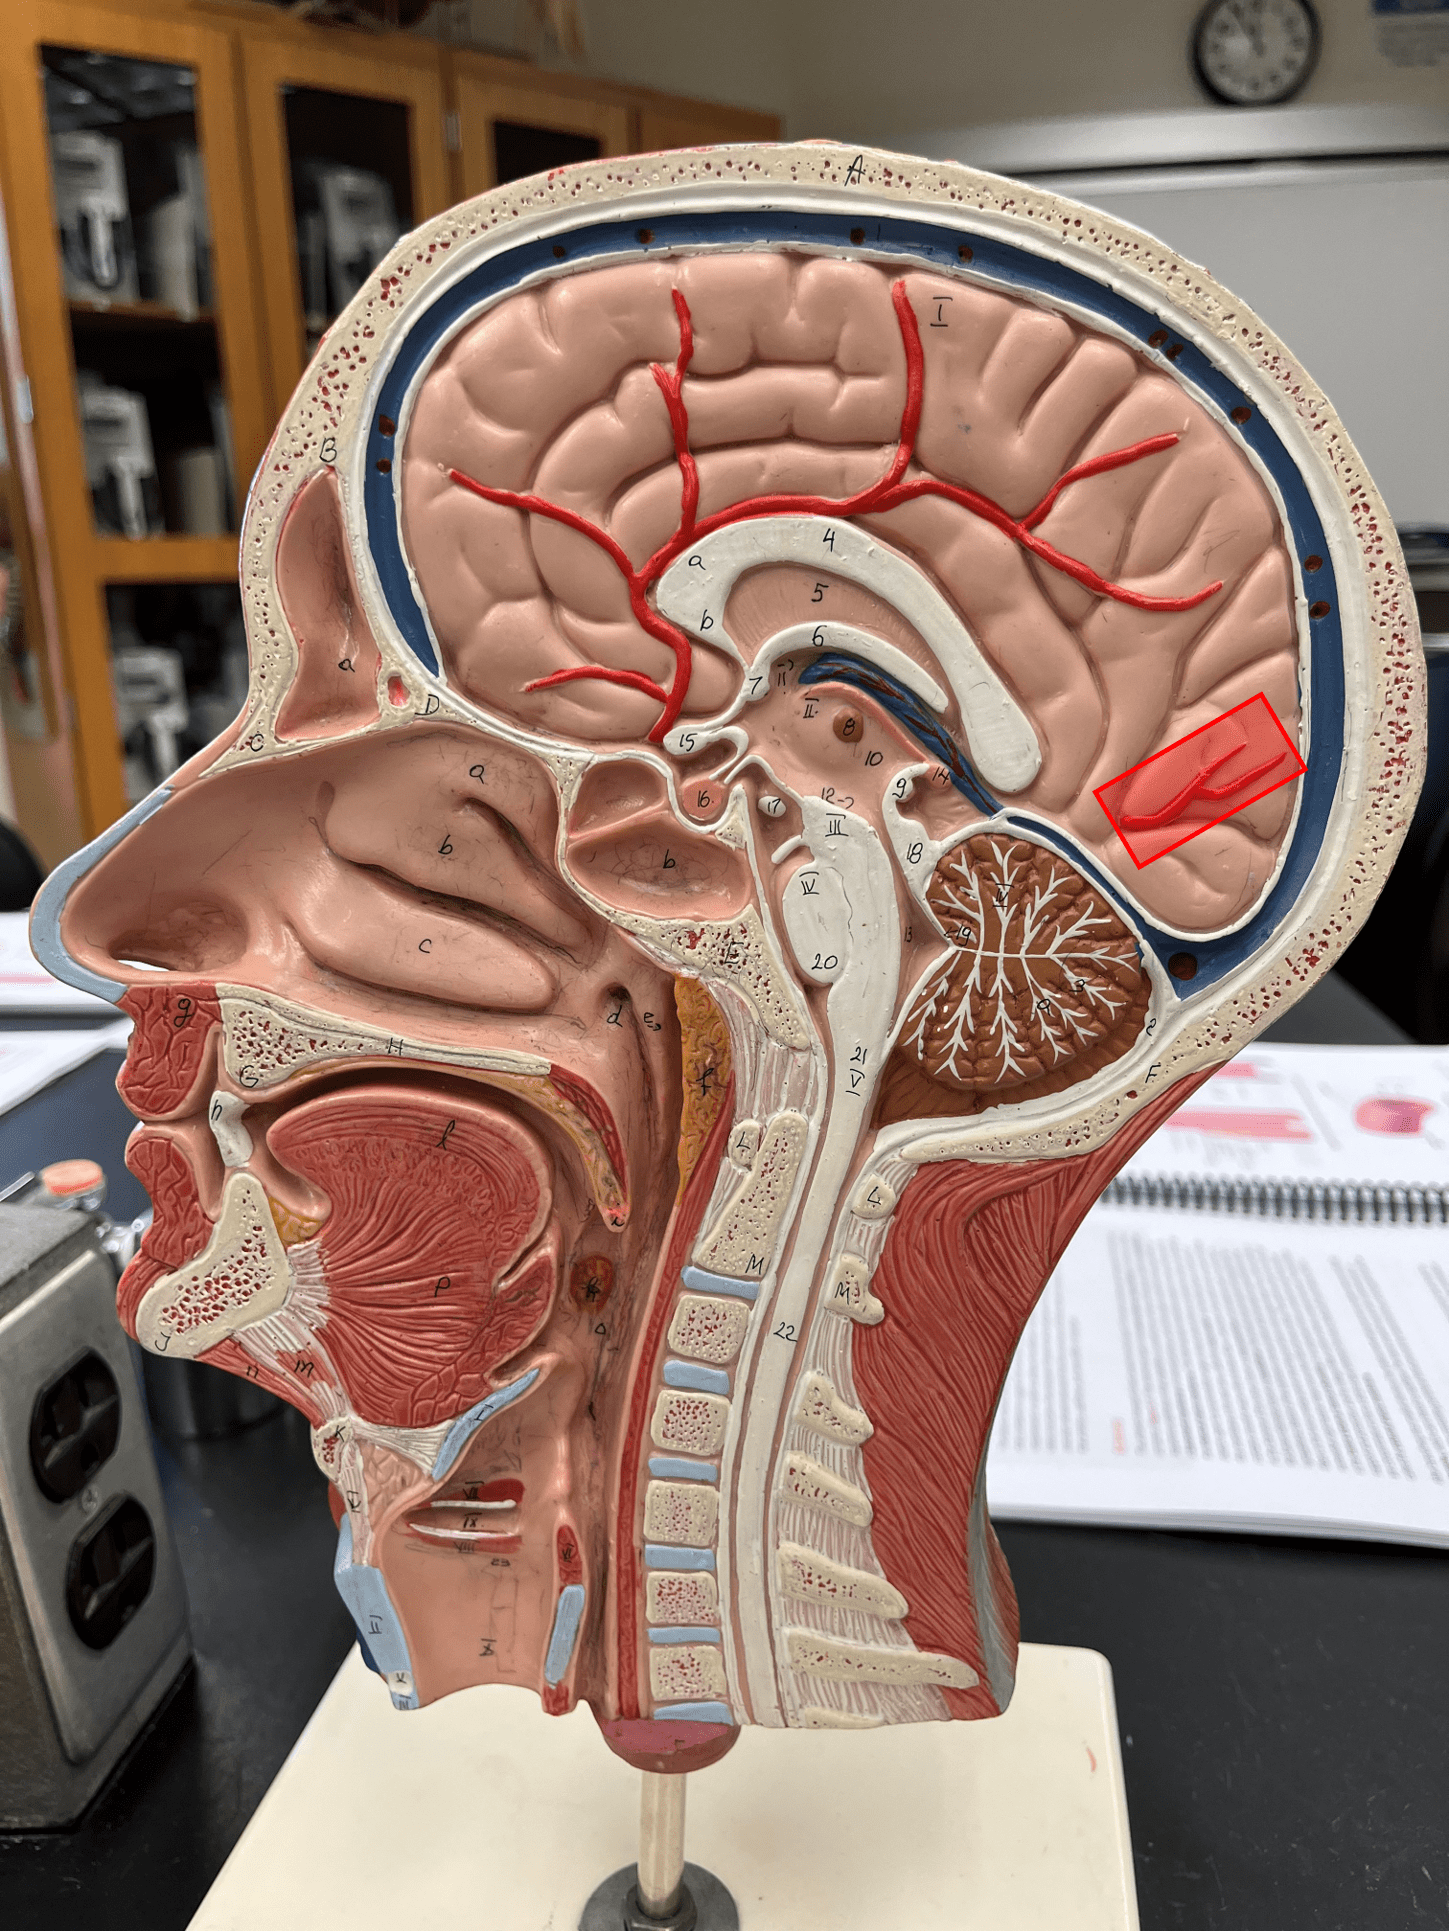

posterior cerebral artery

• An artery of the cerebral circulation.

• Originates from the basilar artery.

• Supplies the temporal and occipital lobes, midbrain, and thalamus.

• Originates from the basilar artery.

• Supplies the temporal and occipital lobes, midbrain, and thalamus.